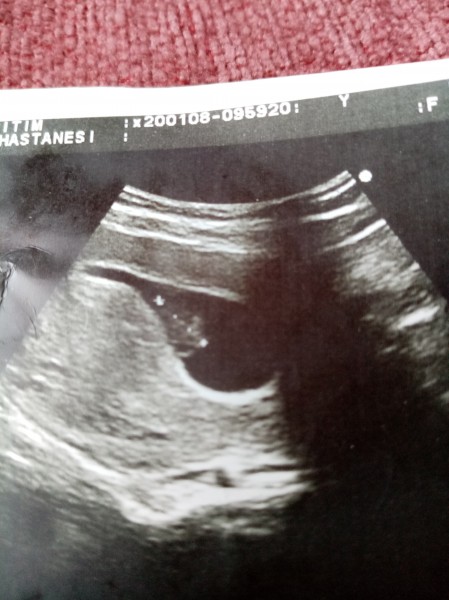

Arkadaşlar dün doktora gittim çok şükür kalp atışını duyduk ama merak ettiğim şey genelde gördüğüm keserler yuvarlak falan oluyo benim ki biraz farklı geldi bna acaba neden olabilir düşük riski war üç öğün progestan kullanıyorum doktor bişiy söylemedi bu konuda

Gebelik haftası 8+5